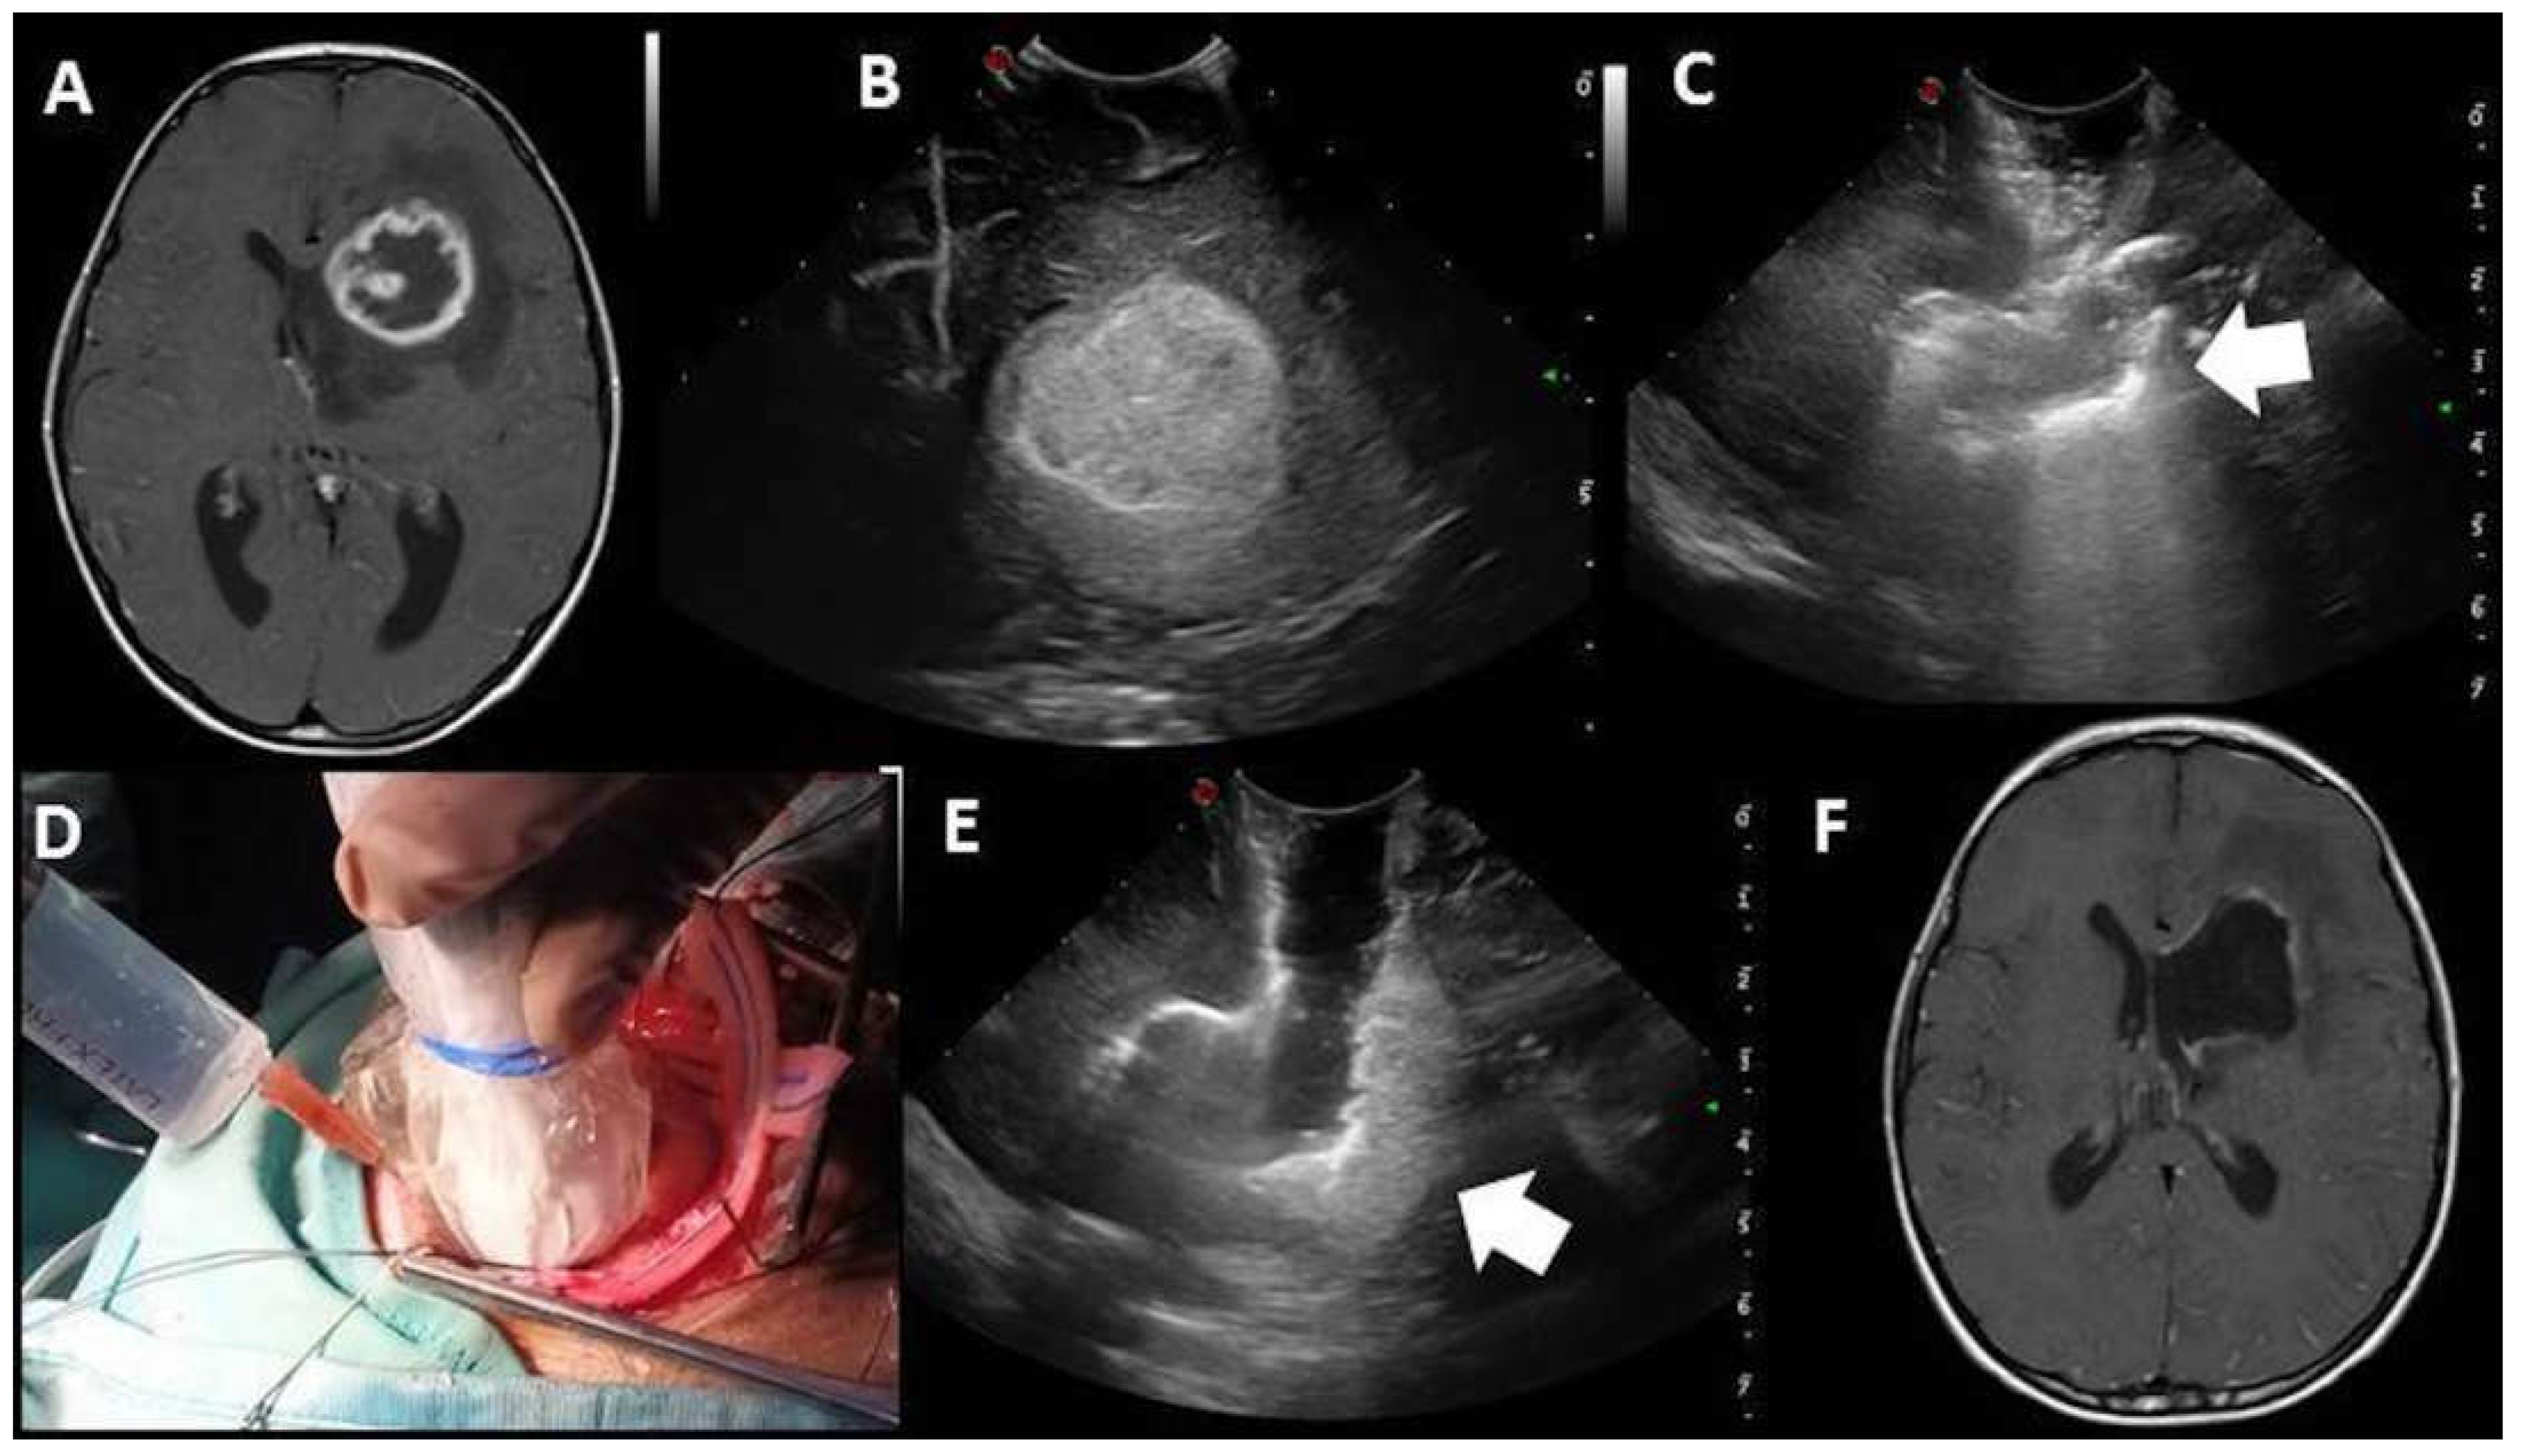

| Post-IOUS | ||

| EOR | Collapsed surgical cavity |

|

| EOR | Open ventricle |

| EOR | Artifacts |